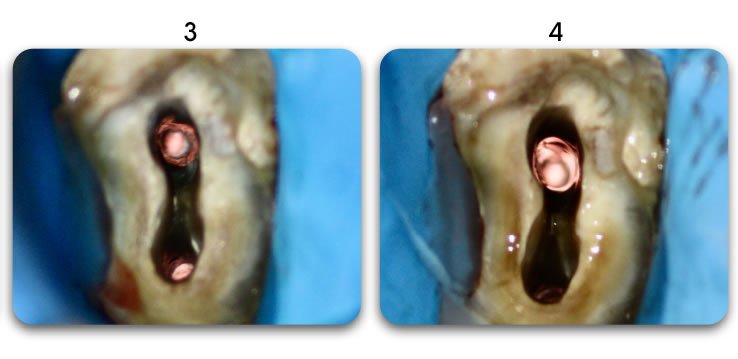

Excellent light transmission

Excellent light transmission for use with dual-cure resins, Biolight DUAL offer excellent light transmission through the optic fiber material.